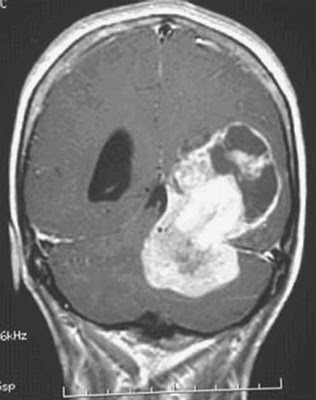

She told me, "Well, there really isn't anything we can do for you here, in my office. I need you to go to a Specialist and get a CAT Scan." Nowadays, they are called a CT Scan for short. It is an X-ray image made using computerized axial tomography.

I checked in, and found my Doctor already in my room waiting for me, looking at my CT Scan. "Jim, sit down. We need to talk." So I sat down and asked my Doctor, "What's up? You're scaring me Doc." She looks at me somberly and says, "I'm sorry Jim. You should be scared. You have an inoperable brain tumor and I would estimate that you only have a month to live!"

I checked in, and found my Doctor already in my room waiting for me, looking at my CT Scan. "Jim, sit down. We need to talk." So I sat down and asked my Doctor, "What's up? You're scaring me Doc." She looks at me somberly and says, "I'm sorry Jim. You should be scared. You have an inoperable brain tumor and I would estimate that you only have a month to live!"

She told me, "Well, there really isn't anything we can do for you here, in my office. I need you to go to a Specialist and get a CAT Scan." Nowadays, they are called a CT Scan for short. It is an X-ray image made using computerized axial tomography.

I checked in, and found my Doctor already in my room waiting for me, looking at my CT Scan. "Jim, sit down. We need to talk." So I sat down and asked my Doctor, "What's up? You're scaring me Doc." She looks at me somberly and says, "I'm sorry Jim. You should be scared. You have an inoperable brain tumor and I would estimate that you only have a month to live!"